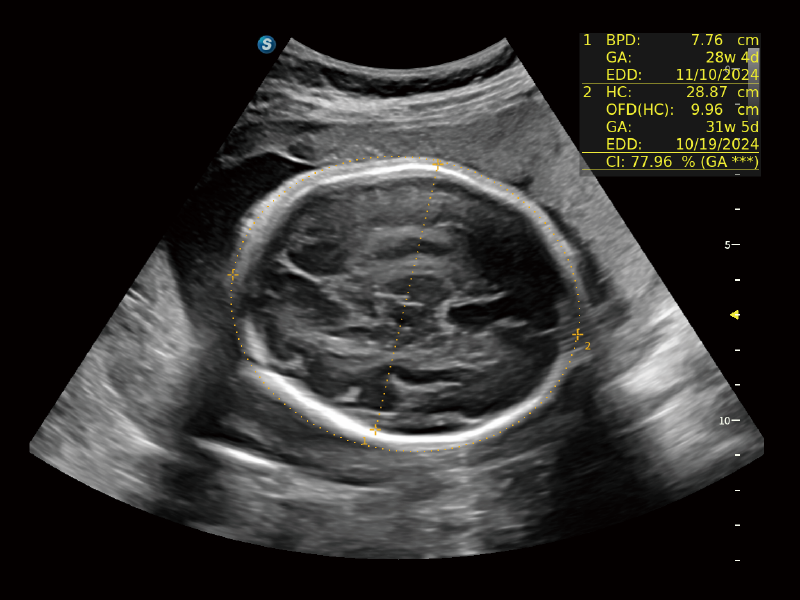

高清無損放大下的NT自動(dòng)測(cè)量

S-Fetus? 鳳眼

胎兒顱腦融合

S-Fetus? 鳳眼(A4C切面)